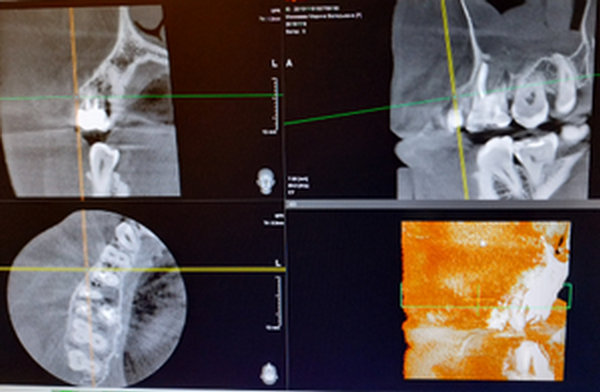

У меня обнаружили 2 кисты на 36 зубе. На одном корне киста маленькая, на втором большая. Снимок прилагается. Врач-терапевт сначала сказал, что нужно удалить кисту, а потом сказал лечить. Просверлил зуб, оставил открытым, сказал полоскать солевым раствором и принимать Кетарол.